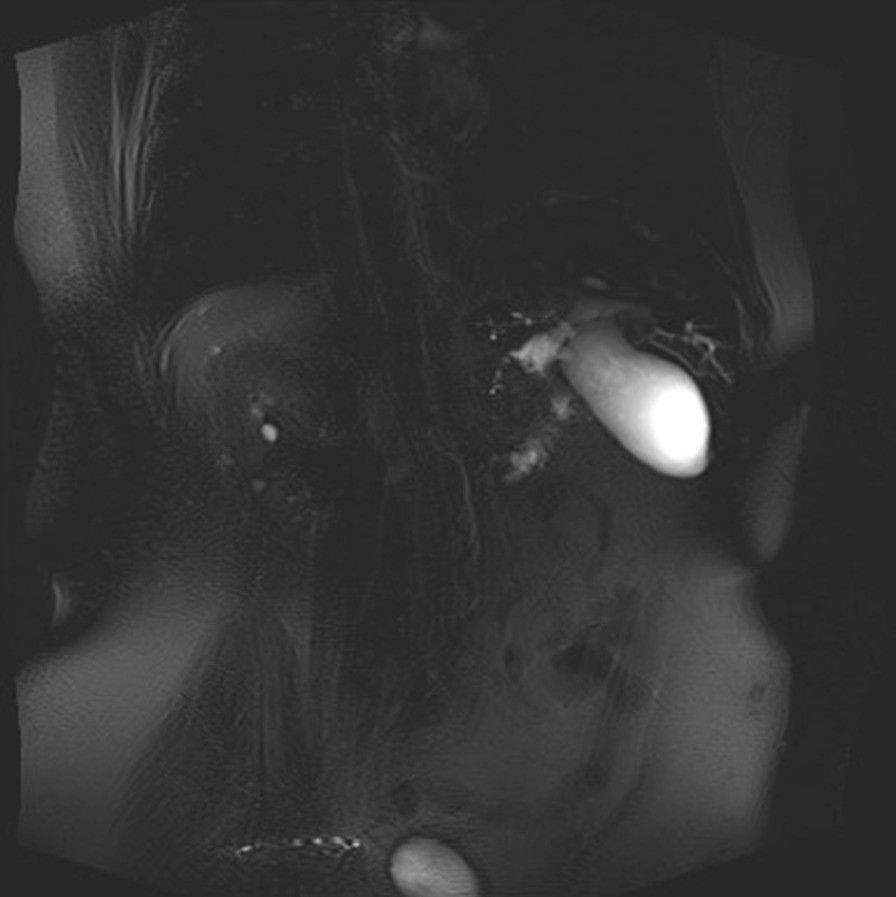

MRI- pre-stenotic common bile duct dilatation